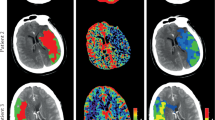

Algorithm development

The training external dataset for UCAs and the detection algorithm used in this study have been described previously12. The UCA detection algorithm consisted of a processing pipeline based on a convolutional neural network (CNN), which was trained from scratch on several thousand three-dimensional (3D) patches extracted from hundreds of time-of-flight MRA source images. The CNN was used to classify each 3D patch as either a non-aneurysm or an aneurysm.

The algorithm pipeline was as follows: vessel extraction was performed using a thresholding method, the 3D volume was resampled to isovoxel, and the principal curvature coefficient was used for extracting key points24. Candidate 3D patches were then extracted around each key point and fed into the CNN. The CNN was a ResNet-1825 composed of 39 convolutional, 1 average pooling, and 1 fully connected layers (Fig. 3), considering inputs of small 3D volumes composed of five slices of 24 × 24-pixel patches and outputs of 0 (non-aneurysm) to 1 (aneurysm) scores. The CNN was coded in Python using the Keras (Tensorflow) library and trained for 100 epochs using the following hyperparameters: learning rate = 0.002, beta_1 = 0.9, beta_2 = 0.999, epsilon = 0.00000001, and schedule decay = 0.004. All key points with scores below a predefined threshold were removed, and nearby key points were subsequently grouped through a clustering process. For each cluster, the center of gravity of the comprising key points was calculated and used as the coordinate of the final output of the algorithm. We evaluated the results of tuning a parameter in the postprocessing part of the algorithm. When the output of the CNN was close to 1, the algorithm judged that the probability of the candidate being a true aneurysm was higher. We evaluated the effect of excluding candidates based on the CNN output at two different thresholds. The cutoff threshold, which was previously set to 0.5, was increased to 0.8 after April 7, 2019 (Figs. 4 and 5).

ResNet-18 convolutional neural network consisting of 18 blocks of convolutional layers, average pooling with batch normalization concatenated with a convolutional skip connection, and one fully connected layer. The activation function used is a rectified linear unit. Conv2D, 2D convolution layer; dense, dense (fully connected) layer; merge, merge (sum) layer; norm, batch normalization layer; ReLU rectified linear unit.